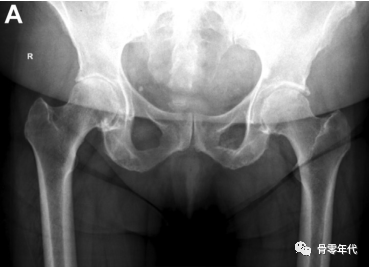

测量肢体长度和偏移量的步骤。首先,使用以下标准获得中性旋转的骨盆前后(AP)片是必要的:骶骨中心应与耻骨联合中心对齐,骨盆倾斜度不应与患者的站立AP片有显著差异。两个股骨应该处于类似的小粗隆侧貌所示的相同的旋转度。两条腿的外展程度应相当,且屈曲程度相同。

然后画一条水平线连接两个泪滴的最下面的边缘。对于肢体长度,在小转子上选择一个双侧等效的点,并垂直于水平连接(图A)。为了确定偏移量,然后在每个股骨颈上选择一个点,大约在预期的颈部切口水平。从颈部这一点开始画一条线,平行于泪滴间线到坐骨边缘(图B)。